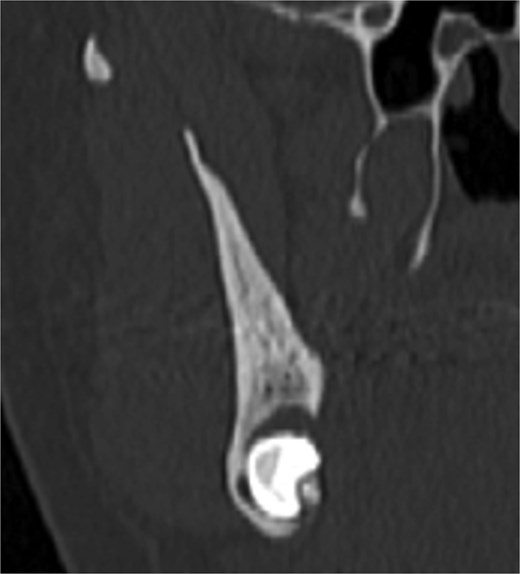

A 49-year-old male patient was referred, after a radiographic finding in a panoramic radiography, for evaluation of the lower right third molar (48) in an ectopic position associated with a radiolucent image, which suggested a cystic lesion (Fig. 1). A cone-beam computed tomography was made. The 3D imaging exams showed the presence of tooth 48 in the mandibular base, in the right angle region, associated with the radiolucent image, lingual fenestration, and intimate relationship between the third molar and the mandibular canal (Fig. 2). Due to the dental position, to have better visualization and less morbidity a submandibular extraoral approach was planned. The tooth removal and cyst curettage were made through the Risdon approach (Fig. 3). A fixation system with reconstruction plate (2.4 mm) was used to prevent a mandibular pathological fracture (Fig. 4). Anatomopathological examination of the cystic capsule was performed with a diagnosis of dentigerous cyst. In the postoperative period, the patient reported alteration in the sensitivity of the inferior alveolar nerve. Postoperative radiographic examinations showed adequate adaptation of the fixation system and complete surgical removal of the tooth and associated lesion. Orthopantomography with 4 months follow-up showed bone repair and adequate adaptation of the fixation system (Fig. 5).

The ectopic third molar usually is asymptomatic and difficult to identify. However, the clinical symptoms include swelling, limited mouth opening, pain, discharging fistula, or temporomandibular joint discomfort [4, 6, 10]. The diagnosis of ectopic third molar is completely formed with radiographic findings such as panoramic radiograph or computerized tomography, that performs 3-dimensional information and precise location of the ectopic tooth and surrounding structures [5, 11]. The panoramic radiography showed the location of the third molar in the present case, but only after the cone-beam tomography examination the treatment plan was defined. The lingual position, the close relationship with the mandibular canal and the caudal position determined the removal through the submandibular approach.